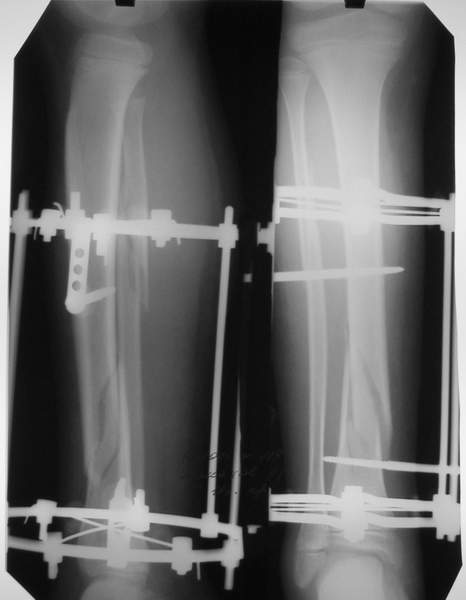

Уважаемый Виталий Евгеньевич,

Помятуя наш недавний разговор о фиксации м.б. кост, высылаю послеоперационные картинки..

Напомню- разбирали случай 17 летнего молодого человека перелом дист тиб.фиб. хирургия после 3 недель с момента травмы( безуспешные попытки закрытой репозиции) Раны заживают первичным натяжением, занимается физиотерапией, пока никаких проблем не наблюдается

Как ты тут оцениваешь восстановление оси большеберцовой кости?

Является ли рутинной практикой у вас использовать снимок противоположной конечности как шаблон для измерения осевых отклонений?

Согласный я с тобой:-)) есть остаточная вальгусная деформация (по снимку видно перекрывание дист. фрагментом б.б по латеральной поверхности проксимальноо фагмента на 2-3 мм и наружная лодыжка репонирована с укорочением, судя по прямой проекции. Необходимость использования интраоперационно дистрактора была бы оправдана (вручную было непросто *вытянуть* дистальный отломок.)

> Является ли рутинной практикой у вас использовать снимок

> противоположной конечности как шаблон для измерения осевых

> отклонений?

Нет, рутинным не назовешь, в данном случае отклонение оси видно и невооруженным взглядом без сравнения со здоровой стороной. Сравнительную осевую оценку со здоровой стороной использую только при планировании коррегирующих остеотомий.